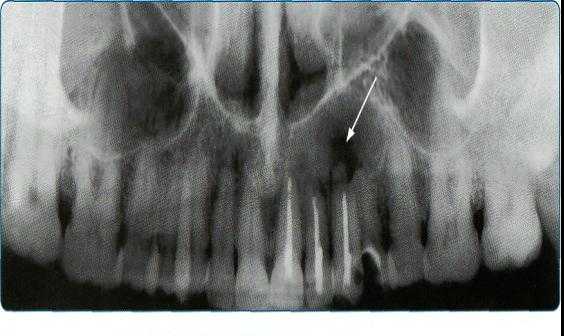

Прямые панорамные рентгенограммы имеют преимущество перед внутриротовыми снимками по богатству деталями изображения костной ткани и твердых тканей зубов. При минимальной лучевой нагрузке они позволяют получить широкий обзор альвеолярного отростка и зубного ряда, облегчают работу рентгенолаборанта и резко сокращают время исследования. На этих снимках хорошо видны полости зуба, корневые каналы, периодонтальные щели, межальвеолярные гребни и костная структура не только альвеолярных отростков, но и тел челюстей. На панорамных рентгенограммах выявляются альвеолярная бухта и нижняя стенка верхнечелюстной пазухи, нижнечелюстной канал и основание нижнечелюстной кости.

На основании панорамных снимков диагностируют кариес и его осложнения, кисты разных типов, новообразования, повреждения челюстных костей и зубов, воспалительные и системные поражения. У детей хорошо определяется состояние и положение зачатков зубов.

Ортопантомограммы демонстрируют взаимоотношения зубов верхнего ряда с дном верхнечелюстных пазух и позволяют выявить в нижних отделах пазух патологические изменения одонтогенного генеза.